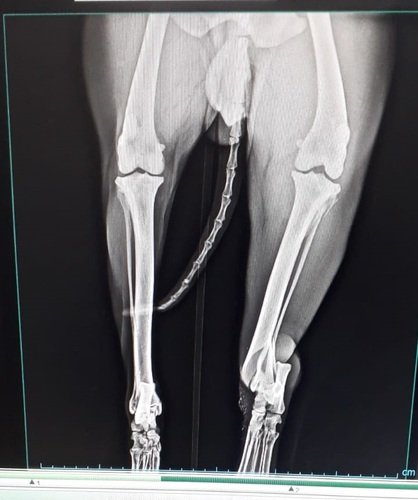

Radiografias antes